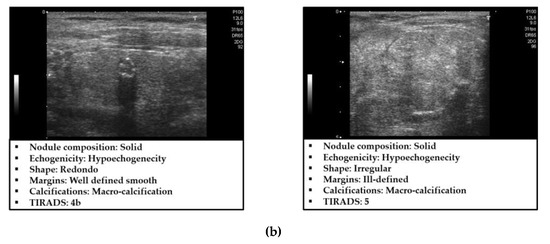

3.1. Dataset and Experimental Setups